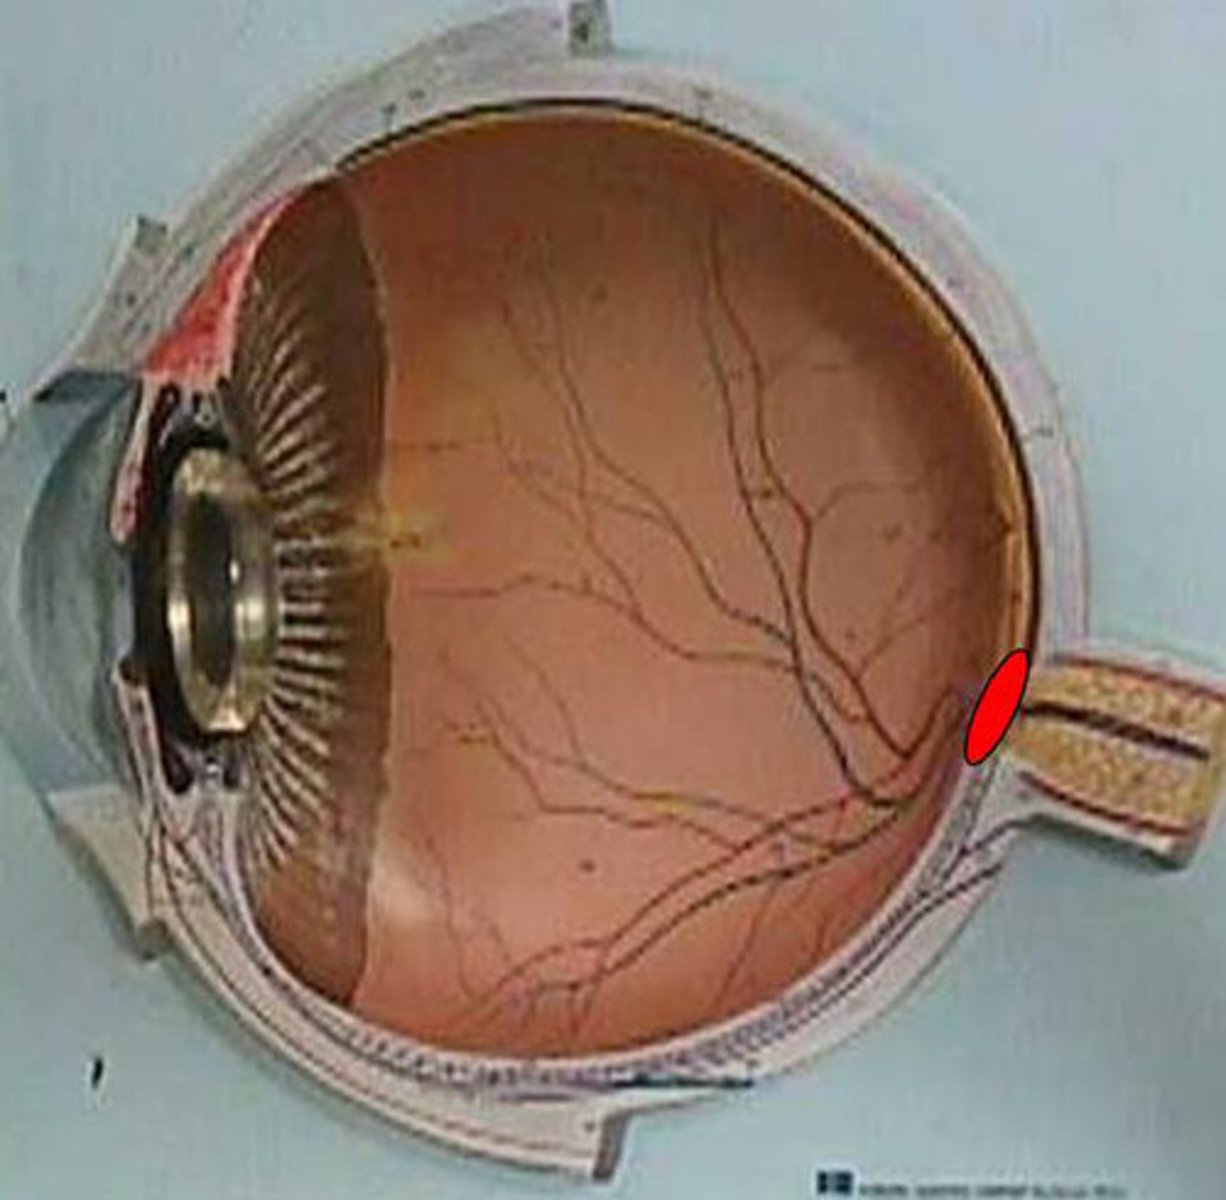

anterior cavity (of eye)

iris

optic disk (blind spot)

choroid

ciliary body

ciliary process

conjunctiva

cornea

fovea centralis

suspensory ligaments

vitreous humor

lens

macula lutea

posterior cavity (of eye)

pupil

retina

sclera

optic nerve